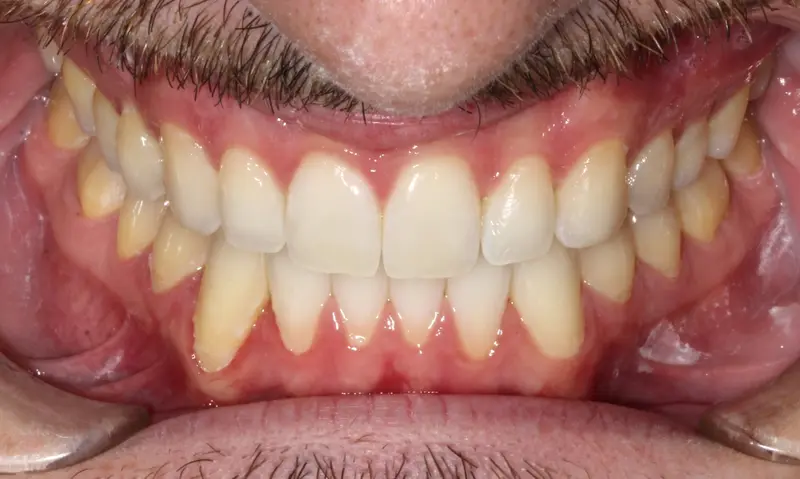

After treatment: The Extraction Myth

After

Before treatment: The Extraction Myth

Before

Bimaxillary protrusion (teeth flaring forward) causing lip incompetence. The patient struggled to close his lips comfortably, straining the chin muscle (mentalis).

A strategic extraction plan (4 premolars) allowed us to retract the front teeth. Note the dramatic improvement in chin projection and facial balance. The extractions did not flatten the face; they harmonized it.